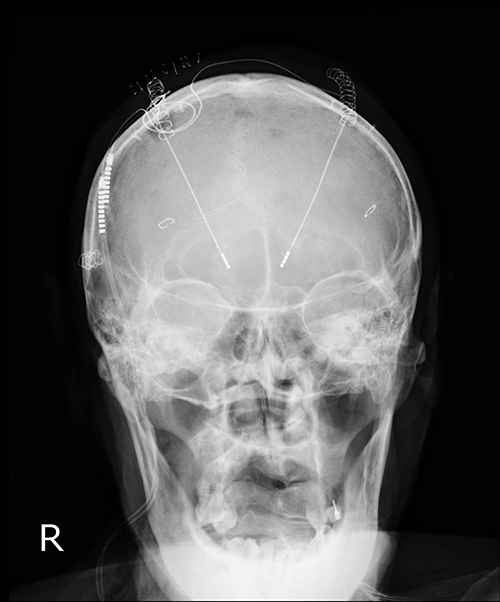

パーキンソン病で手術を行った患者さんのレントゲン

- パーキンソン病

- 本態性振戦

痛みやふるえ・てんかんが該当します。診察し、MRI検査などを行い、投薬治療 (主に内服薬での治療)や手術を行います。

パーキンソン病や本態性振戦などは、はじめは投薬治療が行われることが多いですが、患者さん本人の状態をみて手術を行うこともあります。